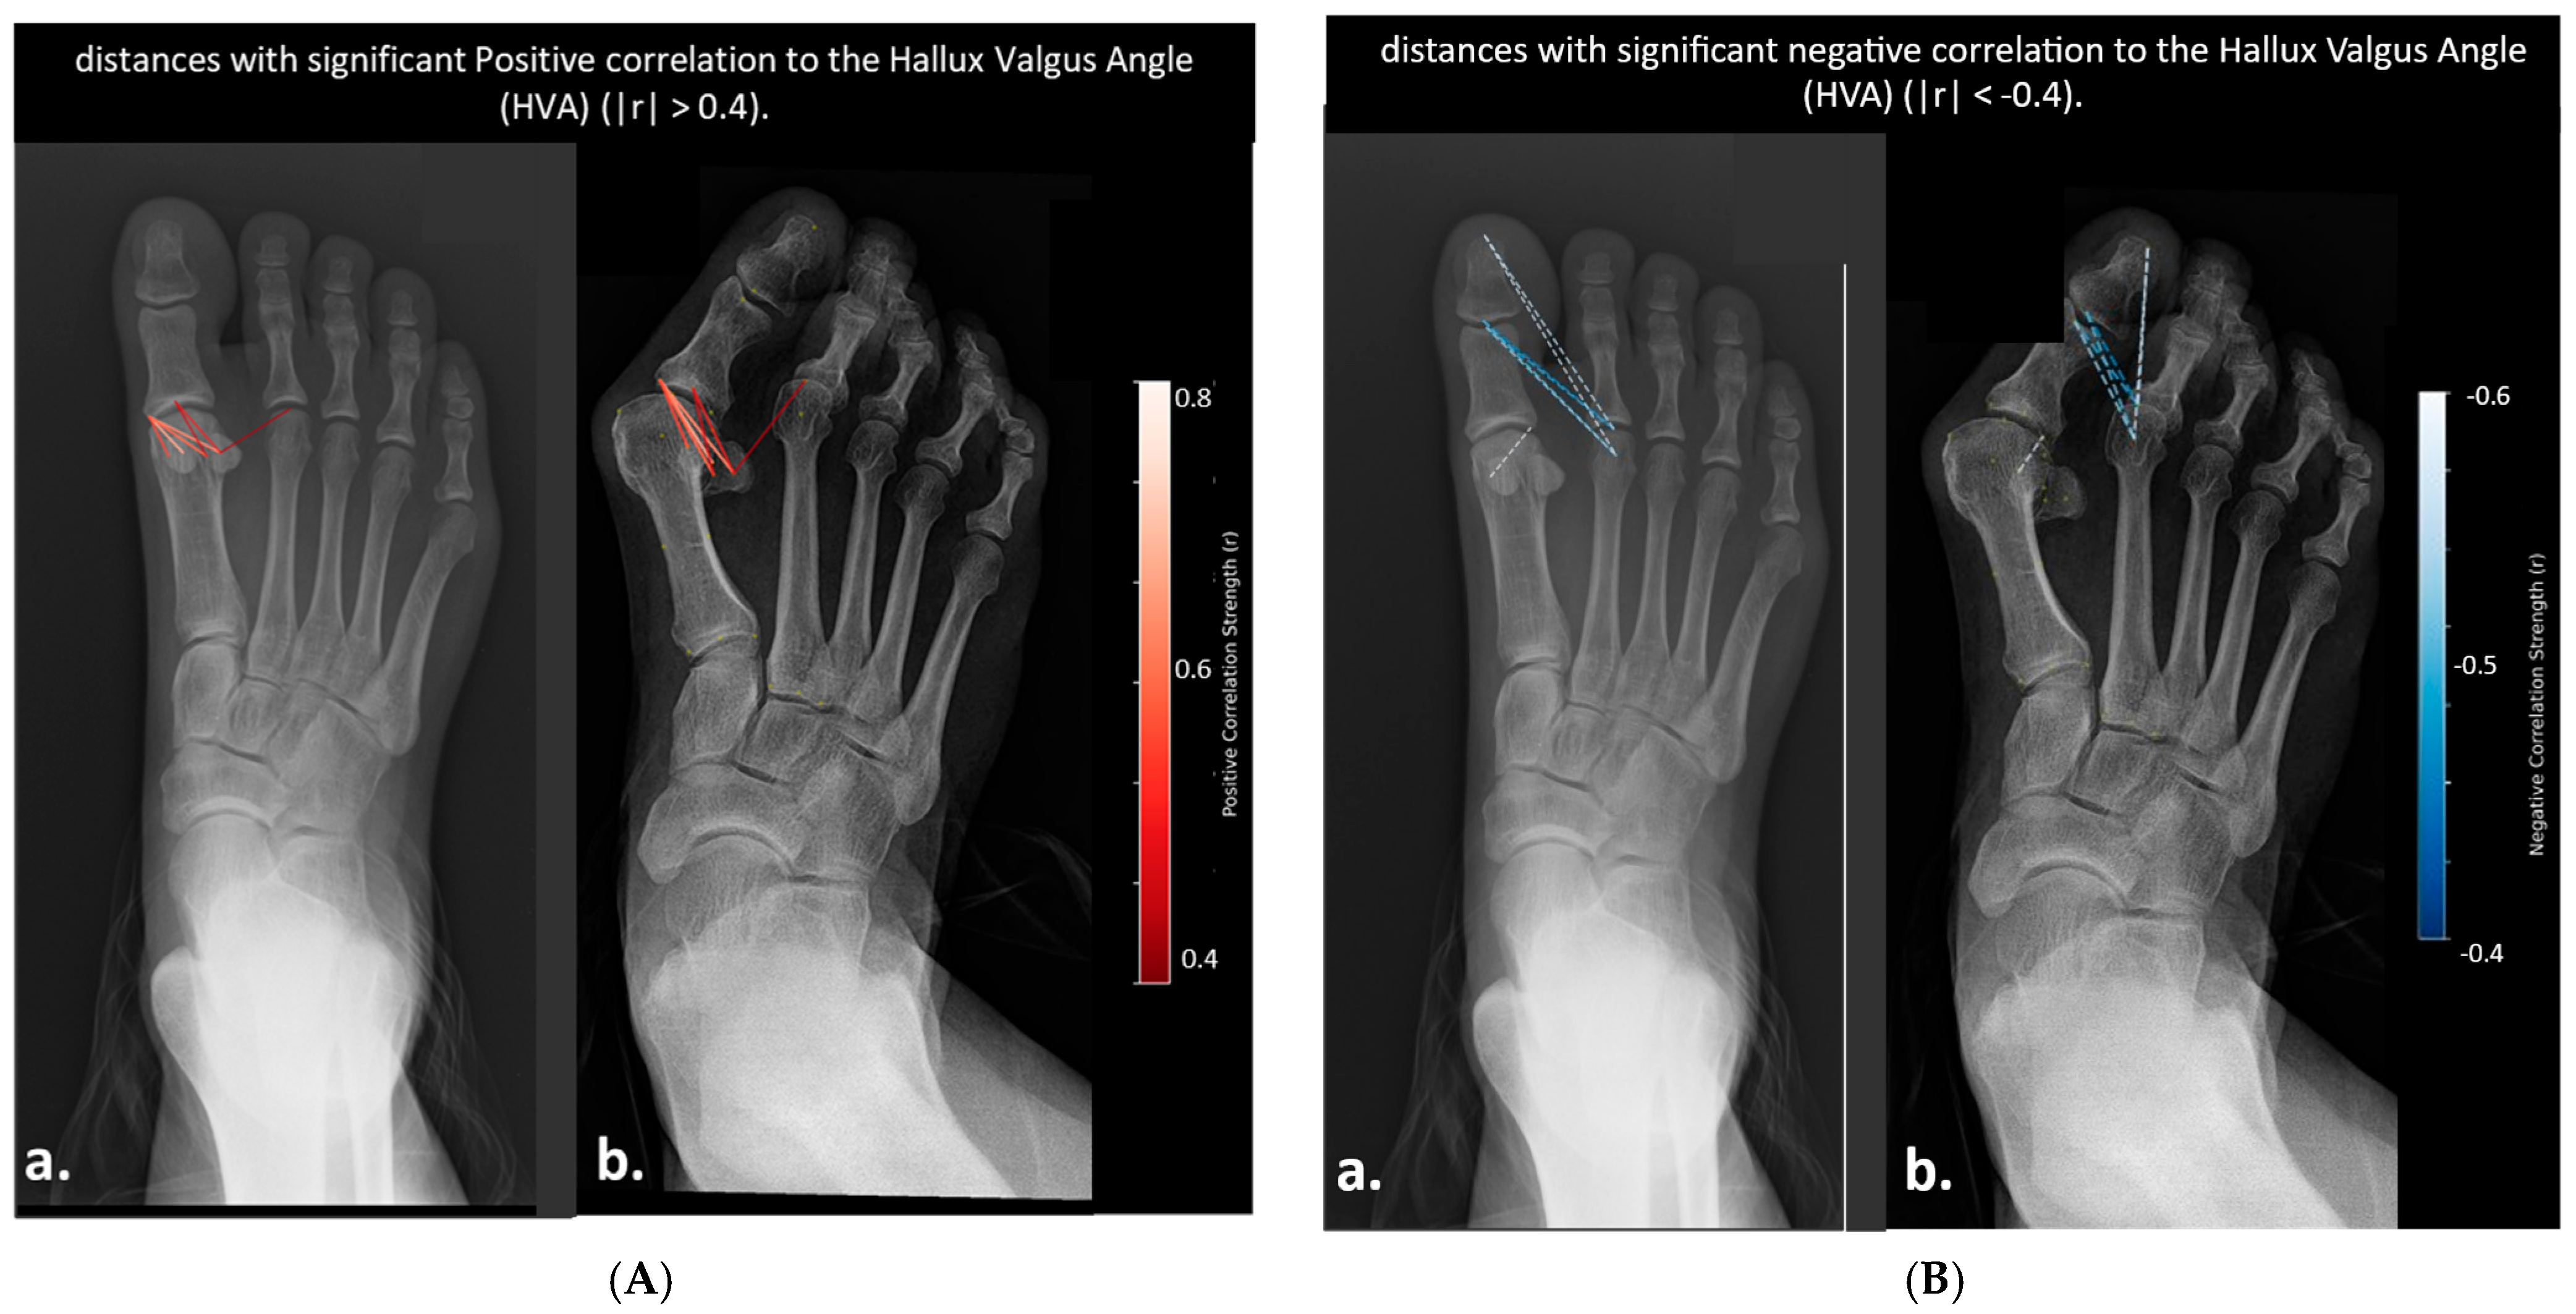

- Color Scale: The gradient ranges from dark blue (−0.6) to dark red (0.6), indicating the strength and direction of correlation (negative to positive).

- Correlation Coefficients: Values are color-coded, with significant correlations (p < 0.05) highlighted. Notable ranges include r > 0.4 for HVA and IMA, and r > 0.3 for DMAA and HIA.

- Annotations: Specific distances (e.g., “2nd metatarsal head to proximal phalanx head,” “Medial sesamoid to proximal phalanx base”) are labeled to reflect anatomical relationships.

- Distances Correlated with Hallux Valgus Angle (HVA)